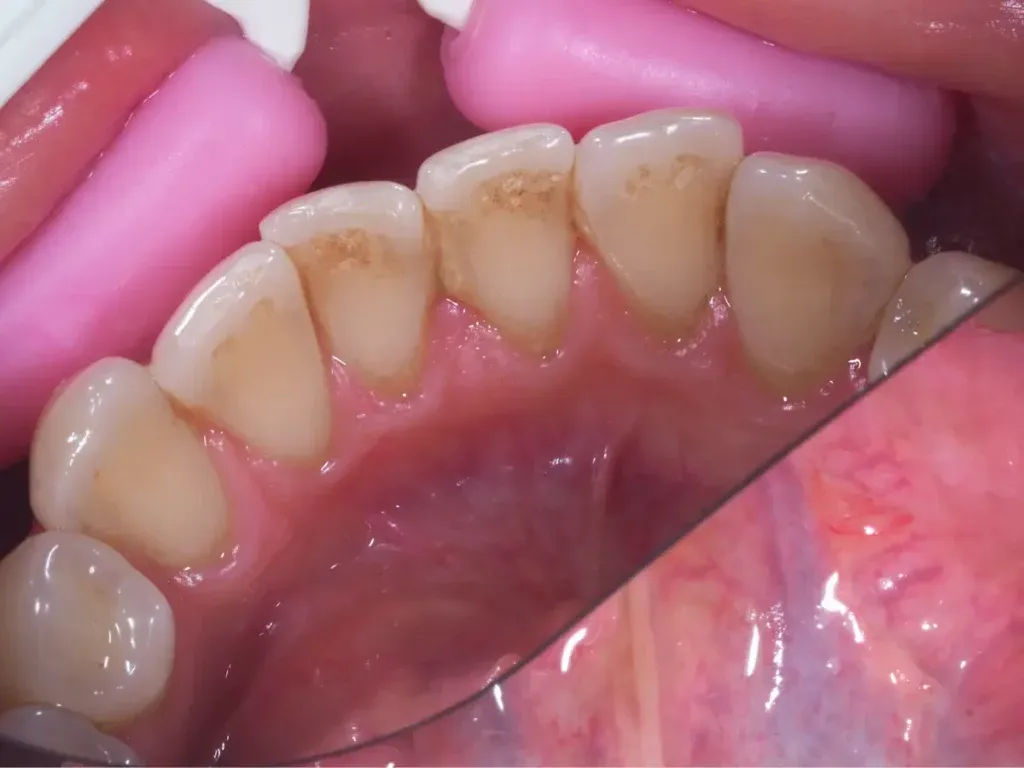

Objawy i skutki osadu na zębach u dzieci

Rodzice powinni zwracać uwagę na objawy osadu na zębach swoich dzieci. Do najczęstszych należą: przebarwienia, nieprzyjemny zapach z ust oraz nadwrażliwość zębów. Dzieci mogą skarżyć się na ból podczas jedzenia słodyczy lub picia zimnych napojów. Jeśli osad nie zostanie usunięty, mogą wystąpić poważniejsze skutki, takie jak próchnica i choroby dziąseł. Dlatego tak istotne jest, aby regularnie kontrolować stan zębów dziecka i podejmować odpowiednie kroki w celu ich ochrony.Jakie techniki szczotkowania pomagają w usuwaniu osadu